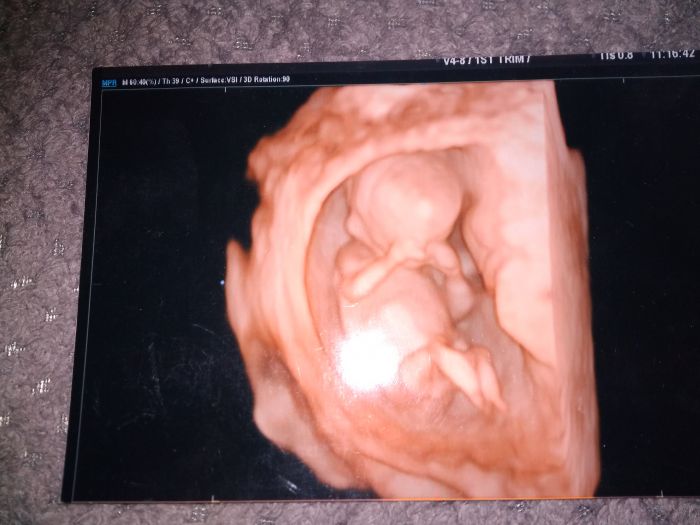

Pak jsem byla 9+1 (přikládám fotku ) a to jsme oznámili rodině těhotenství.

Pak jsem byla 13+0 na screeningu (taky hodím fotku)